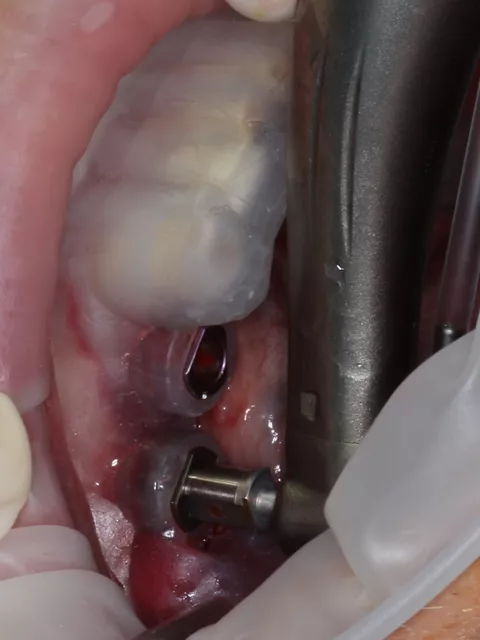

Similarly, at LL6 the implant exhibited insufficient primary stability (< 20 N·cm) and was placed subcrestally with a cover screw for submerged healing, while the mesial implant at LL5 (when stability was adequate > 45 N·cm) received a HealFit® abutment to support soft‑tissue maturation during healing (7.).

7. Distal implant placed with a cover screw, and mesial implant restored with a HealFit® SH anatomical healing abutment.

7

Suturing was adapted to each implant site. The distal implant was fully submerged with a cover screw, requiring complete primary closure. At the mesial implant, where a HealFit® SH abutment was placed, only two simple interrupted sutures were placed mesially and distally to stabilize the soft tissues.

8. Suturing was adapted to each implant site. The distal implant was fully submerged with a cover screw, requiring complete primary closure. At the mesial implant, where a HealFit® SH abutment was placed, only two simple interrupted sutures were placed mesially and distally to stabilize the soft tissues.

8

Three months after implant placement, a second‑stage surgery was performed at the distal site to uncover the implant following successful osseointegration. A standard healing abutment was placed, as this implant had initially been placed subcrestally with a cover screw due to insufficient primary stability and required conventional freehand placement.

In contrast, the mesial implant had achieved adequate primary stability at surgery, allowing the use of a HealFit® SH anatomical healing abutment from the time of placement. This resulted in progressive transmucosal shaping without the need for additional surgical intervention. At re‑evaluation (8.), peri‑implant soft‑tissue maturation was already complete at this site, illustrating the clinical advantages of immediate transmucosal conditioning, including reduced need for second‑stage surgery, minimised soft‑tissue trauma, improved emergence profile development, and a more streamlined prosthetic workflow.